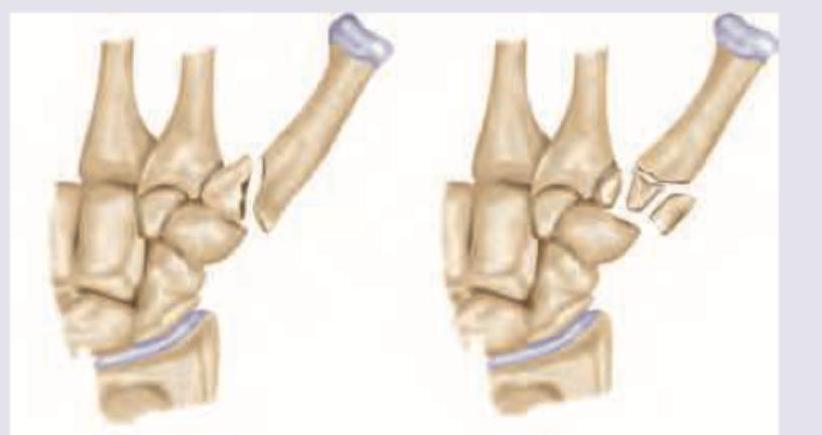

Question 1: What is correct about the fracture shown in the figure?

- A. A= Bennett fracture, B= Rolando fracture (Correct Answer)

- B. A= Rolando fracture, B= Bennett fracture

- C. A= Boxer's fracture, B= Bennett fracture

- D. A= Bennett fracture, B= Boxer's fracture

Explanation: ***A= Bennett fracture, B= Rolando fracture*** * **Bennett fracture** (A) is an **intra-articular fracture** of the base of the first metacarpal bone with a characteristic **two-part fracture** pattern. It involves a small fragment of the metacarpal base remaining attached to the carpometacarpal joint, while the rest of the metacarpal is dislocated. * **Rolando fracture** (B) is a **comminuted intra-articular fracture** at the base of the first metacarpal. It is characterized by a **Y or T-shaped fracture pattern**, indicating a more complex, three-part or more fragment involvement compared to a Bennett fracture. *A= Rolando fracture, B= Bennett fracture* * This option incorrectly identifies A as a Rolando fracture; Image A clearly shows a **two-part fracture** typical of a Bennett fracture, not the comminuted pattern of a Rolando. * Similarly, B is incorrectly identified as a Bennett fracture as it depicts a **multi-fragmented, Y-shaped fracture**, which defines a Rolando fracture. *A= Boxer's fracture, B= Bennett fracture* * **Boxer's fracture** is a fracture of the **neck of the fifth metacarpal**, which is not depicted in either image A or B. Both images show fractures at the base of the first metacarpal. * Image A is a **Bennett fracture**, not a Boxer's fracture, and B is a **Rolando fracture**, not a Bennett fracture. *A= Bennett fracture, B= Boxer's fracture* * While A is correctly identified as a **Bennett fracture**, B is incorrectly identified as a Boxer's fracture. * As previously stated, a **Boxer's fracture affects the fifth metacarpal**, whereas image B clearly shows a fracture of the first metacarpal base with multiple fragments.